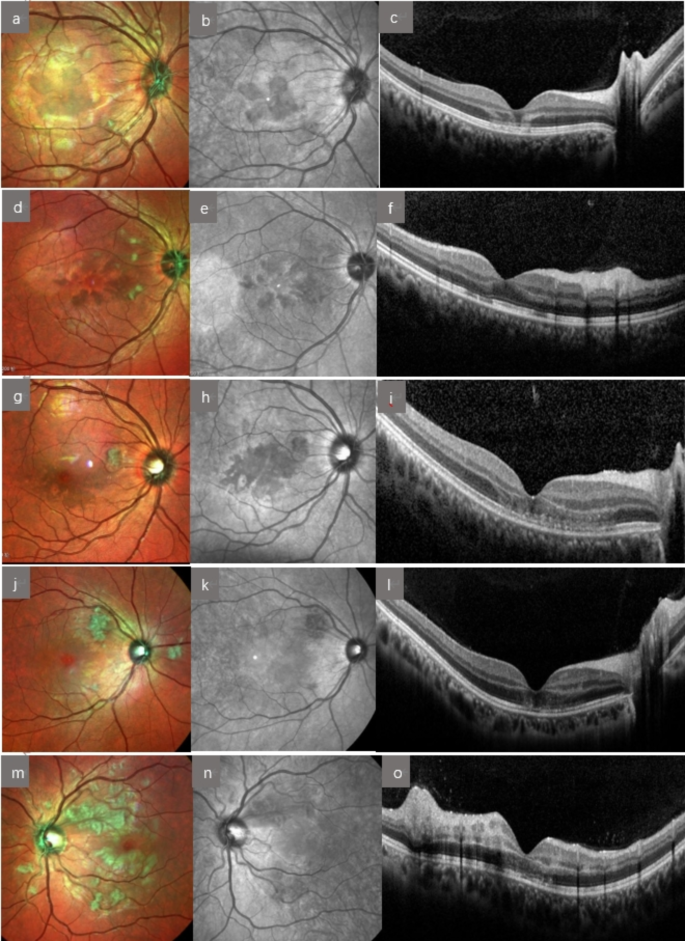

OCT examination(Figure 1): A common characteristic was high reflectivity signals in the outer retinal layer (outer plexiform layer and/or outer granular layer) of the macular area, with some cases showing high reflectivity signals in the inner nuclear layer or even the entire layer. Abnormal changes in reflectivity signals were observed in the ellipsoid zone and interdigitation zone of 33 patients (66 eyes, 68.8%). Macular edema and retinal pigment epithelial detachment were present in 2 cases (4 eyes, 4.2%), and peripapillary nerve fiber layer thickening was observed in 1 case (2 eyes, 2.1%).

(a) Multicolor imaging (MCI): Petal-like deep red changes in the macular area. (b). IR (Infrared): Petal-like low reflective signal in the macular area. (c). OCT (Optical Coherence Tomography): High reflective signals in the outer plexiform and outer nuclear layers. (d)MCI: Wedge-shaped deep red changes in the macular area. (e)IR: Wedge-shaped low reflective signal in the macular area. (f)OCT: High reflective signal in the outer plexiform layer; cotton wool spots corresponding to high reflective signal in the nerve fiber layer. (g)MCI: Patchy deep red changes in the macular area. (h)IR: Patchy low reflective signal in the macular area. (i)OCT: High reflective signal in the outer nuclear layer; irregular reflective signal in the ellipsoid zone. (j)MCI: No obvious abnormalities in the macular area. (k)IR: No obvious abnormalities in the macular area. (l)OCT: High reflective signals visible in the outer nuclear, inner nuclear, and ganglion cell layers. (m)MCI: No obvious abnormalities in the macular area; numerous cotton wool spots. (n)IR: No obvious abnormalities in the macular area. (o)OCT: High reflective signal across the full thickness of the neurosensory retina.

Multicolor imaging (MCI): 23 cases (46 eyes, 47.9%) showed petaloid or wedge-shaped deep red changes in the macular area, while 25 cases (50 eyes, 52.1%) did not exhibit any apparent abnormalities.

Cotton-wool spots were found in 31 cases (54 eyes, 56.3%) in the peripapillary or posterior pole area, and 6 cases (12 eyes, 12.5%) showed a large number of cotton-wool spots. Additionally, 11 cases (19 eyes, 19.8%) presented with scattered hemorrhagic spots around the optic disc, and 1 case (2 eyes, 2.1%) showed optic disc edema.

Cotton-wool spots appeared as areas of high reflectivity in the nerve fiber layer on OCT and as low-fluorescence spots in fundus fluorescein angiography (FFA).

IR examination (Fig. 1): The MCI revealed dark red lesions in the macular area, corresponding to low reflectivity signals. Among the patients without obvious dark red changes in the macular area, no abnormalities were observed in IR.